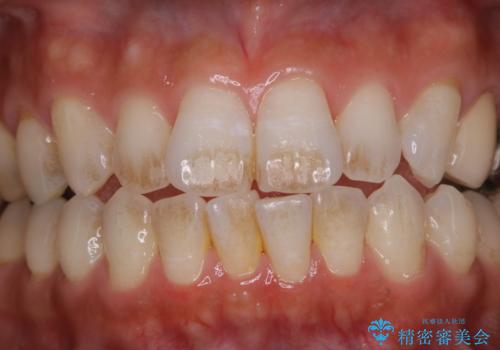

歯についたタバコのヤニをPMTCで綺麗に

- 電子タバコを吸う習慣があり、ステインがついてしまっている見た目が気になるとのことで来院されました。ステインだけではなく、歯石も全体的に付着していたためPMTC60分コースを行いました。

PMTCは、歯に付着した汚れを除去していくため、着色が気になる場合にも行うことができます。ご自身でのセルフケアだけで着色を落とそうとすると、逆に歯を傷つけてしまったり、精密に汚れを除去できないこともあります。また、日常生活で着色しやすい飲食物を避けたりすることはストレスに感じてしまったり、あまり現実的ではありません。

歯科医院にて、適切な処置を行うことで、長期的に安定したお口の環境が作られます。まずはカウンセリングなどもおススメです。